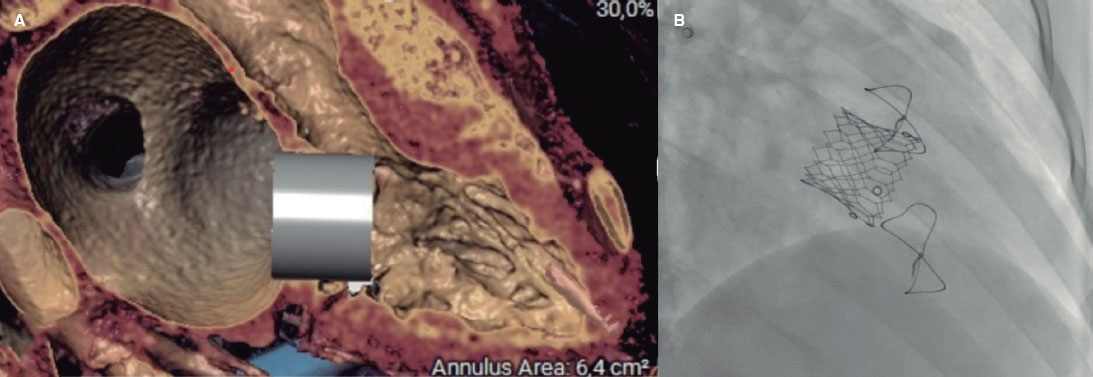

Se optó por un implante percutáneo valve-in-valve. Se realizó estudio con angiografía coronaria por tomografía computarizada con el programa 3Mensio (PIE Medical, Países Bajos), con simulación virtual de prótesis SAPIEN de 29 mm (Edwards Lifesciences, Estados Unidos), considerándose apta, con un área estimada del neotracto de salida del ventrículo izquierdo de 1,8 cm2 (figura 1A).

Figura 1.

Se realizó abordaje transeptal con aguja BRK ecoguiada y dilatación del septo interauricular con balón Atlas (Bard Medical, Estados Unidos) de 16 × 40 mm. Se avanzó el sistema de emplazamiento de la prótesis SAPIEN 3 de 29 mm, implantándola con sobreestimulación simultánea en el ventrículo izquierdo, con excelente resultado (figura 1B, vídeo 3 y vídeo 4 de material adicional).